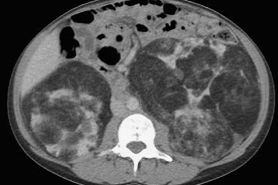

比如淋巴管肌瘤病(LAM),下图是典型影像,呈现弥漫性的薄壁囊肿,病变分布得非常均匀、大小相似:

还可能合并一些肺外表现(如可能会有脑部的改变),但无论有没有结节性硬化症、是散发的还是遗传的,患者都有可能出现有肾脏病变,这点需要注意。

图:淋巴管肌瘤病,TSC相关(结节性硬化症,一种多系统表现的肿瘤性遗传病)